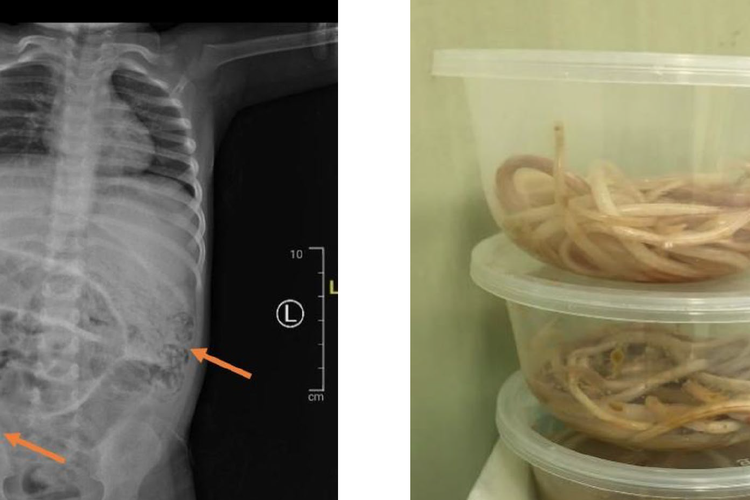

Perut anak di Jember yang dipenuhi cacing hingga tak bisa BAB selama seminggu

(Dokumentasi RSD dr Soebandi Jember)